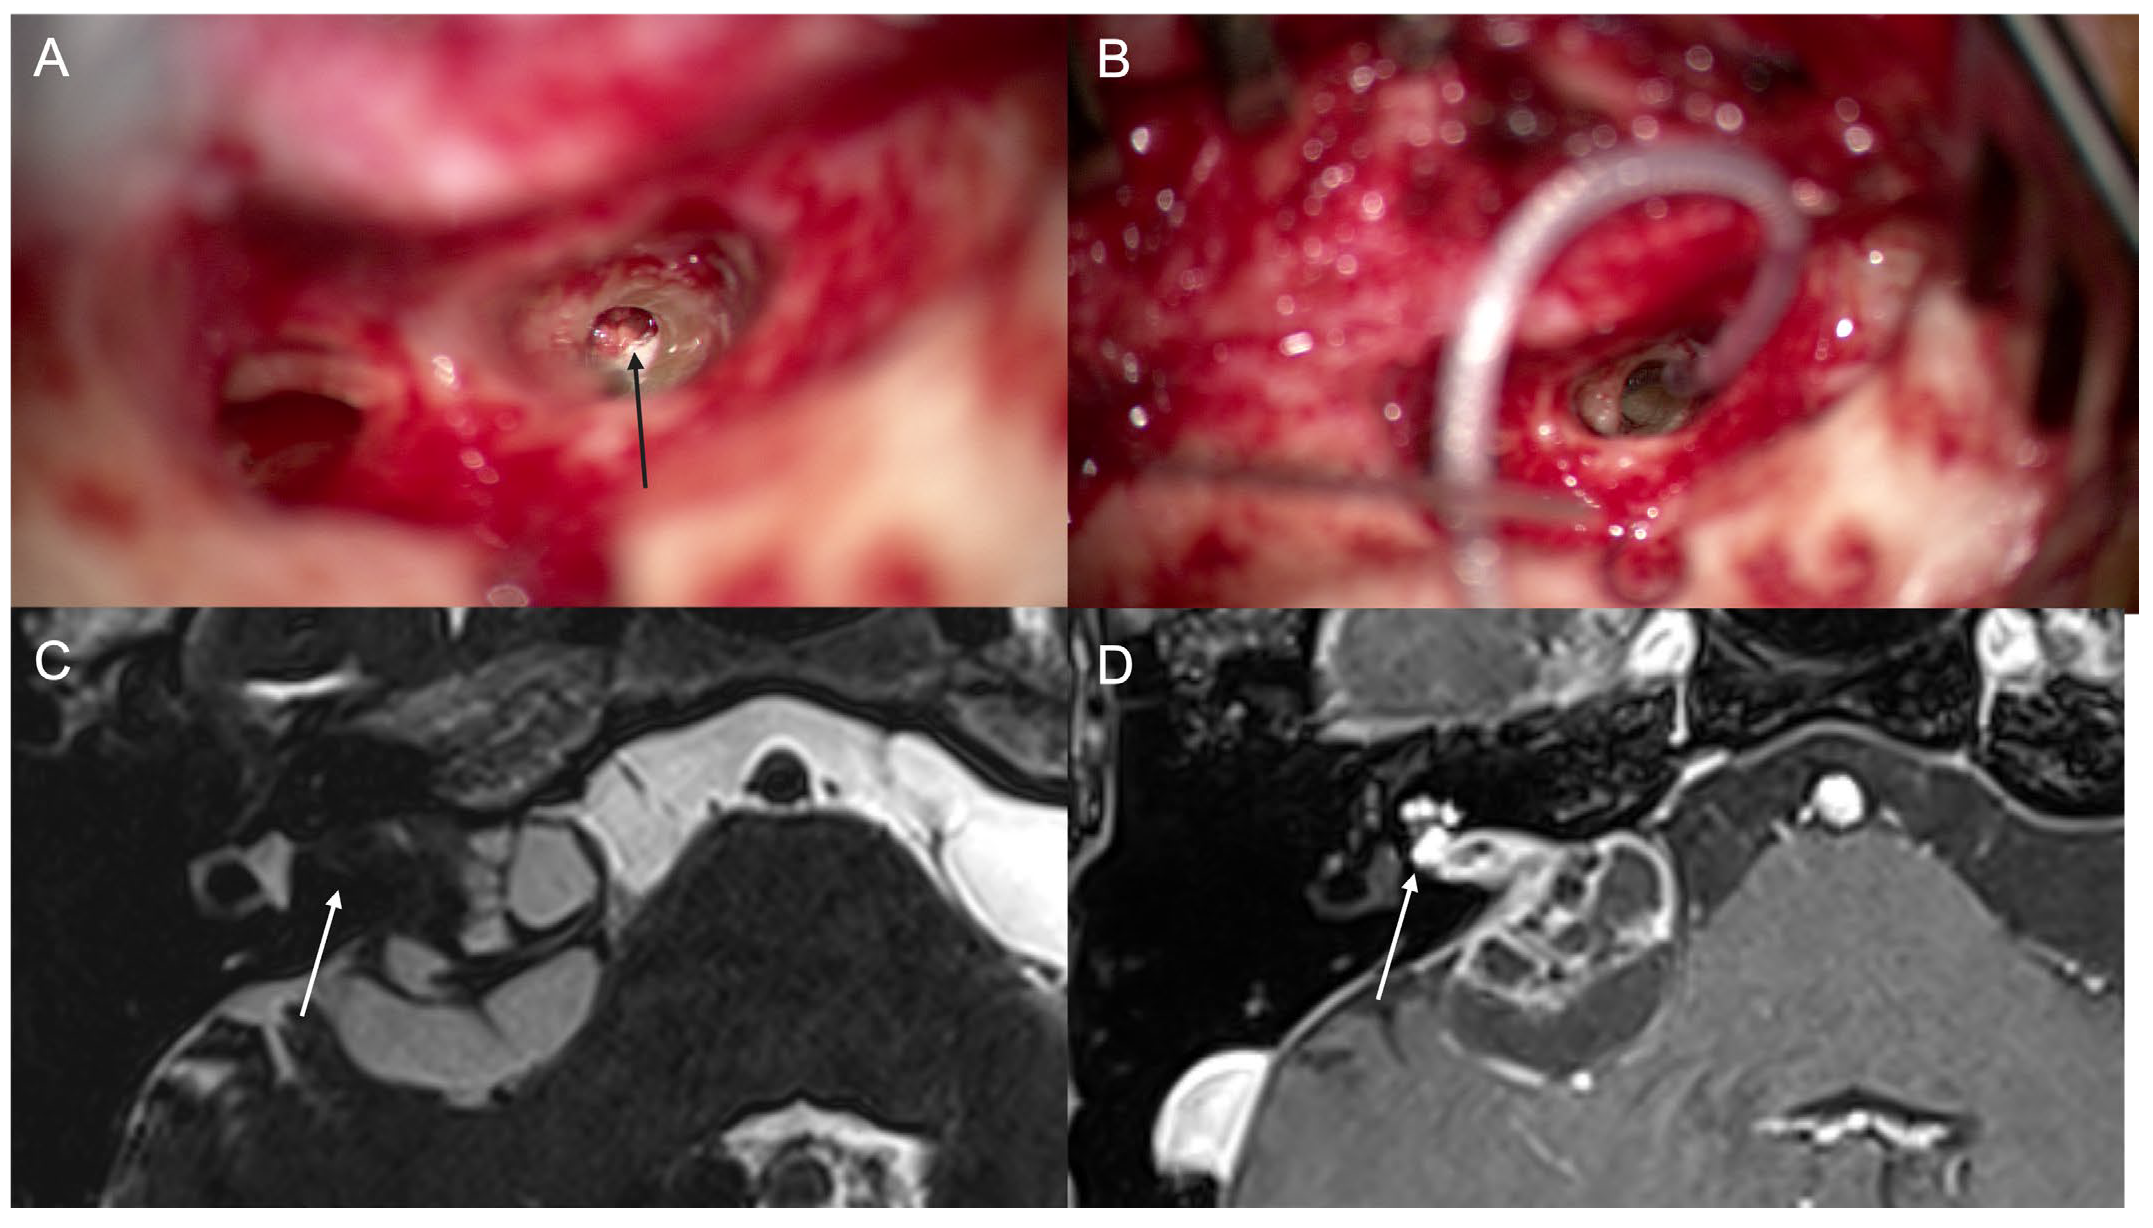

3.4. Case 4